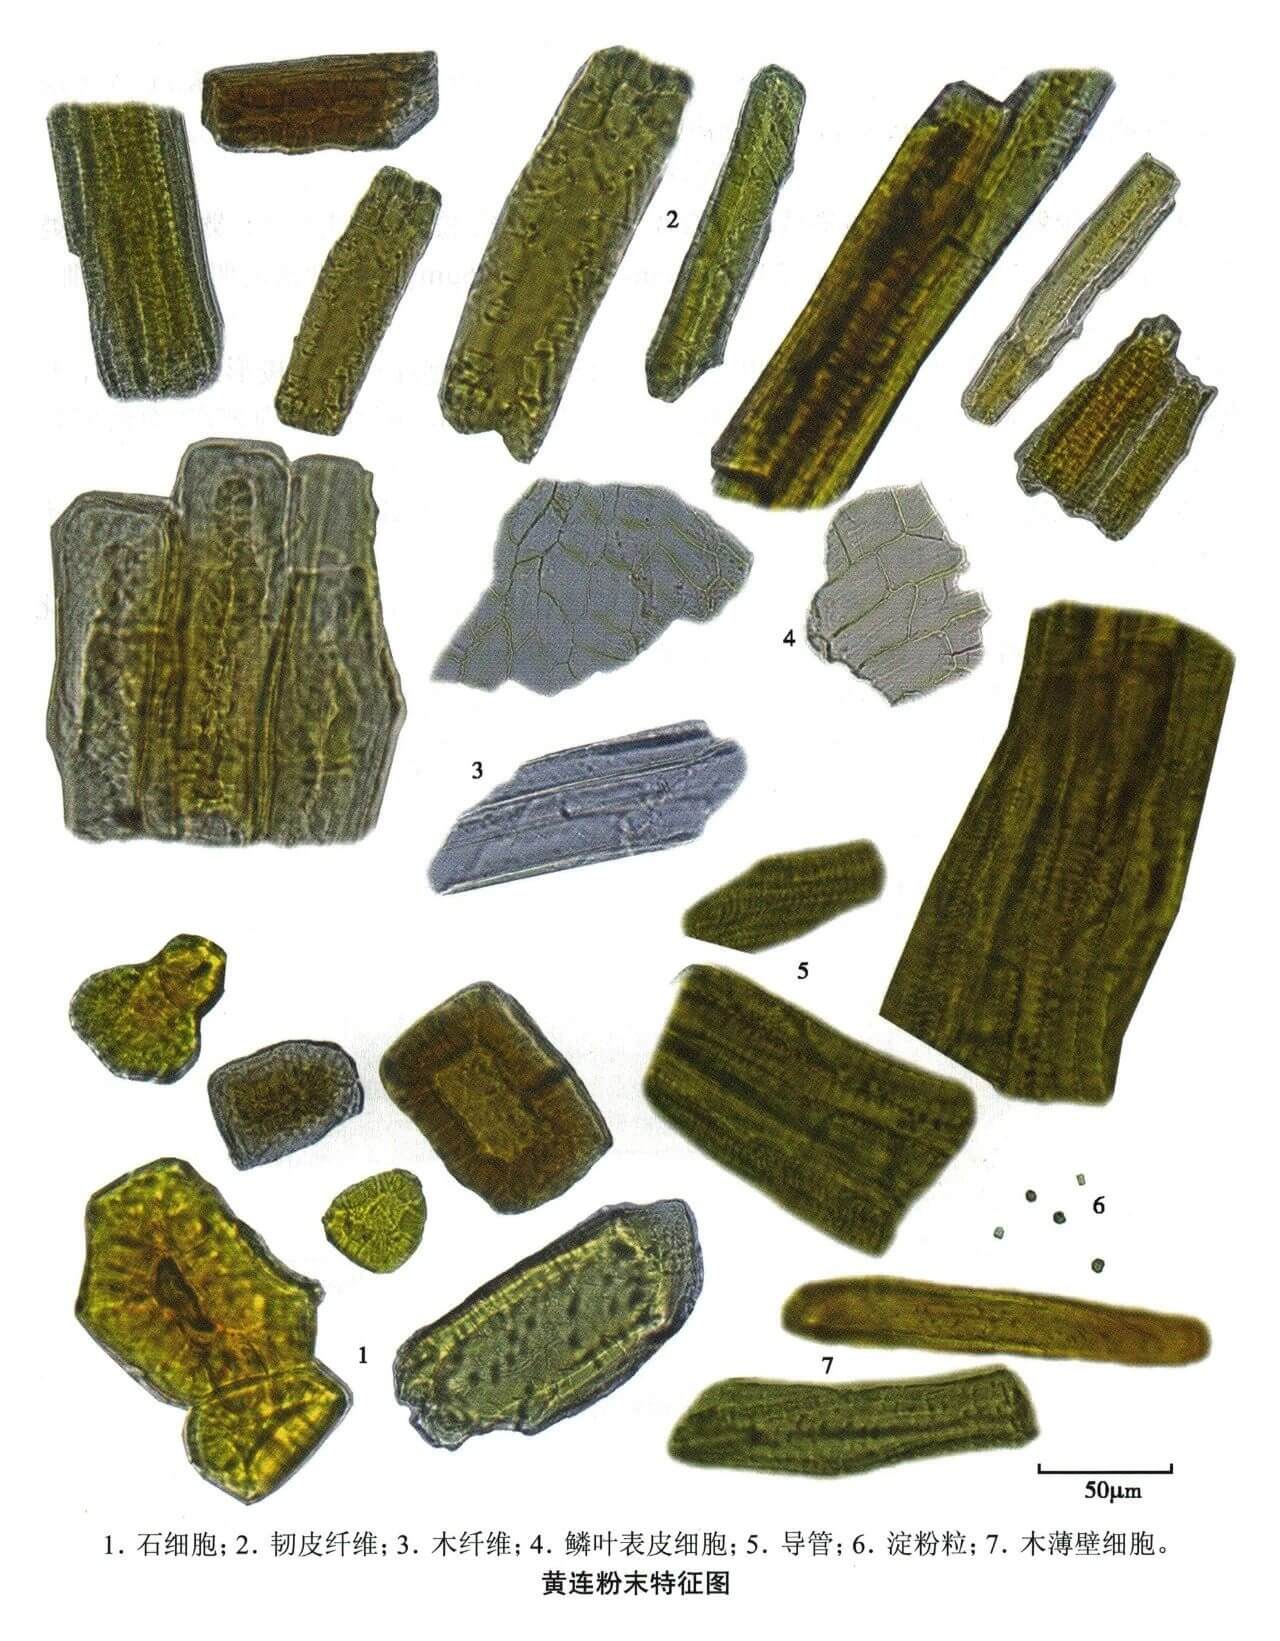

黄连

| 黄连 |

|---|

| 【参考文献】 《中药鉴定学》(康廷国主编) |

| 【显微鉴别】 粉末黄棕色或黄色。石细胞为类方形、类圆形、类长方形或近多角形,直径25~64μm,长至102μm,黄色,壁厚,壁孔明显。中柱鞘纤维黄色,纺锤形或梭形,长136~185μm,直径27~37μm,壁厚。木纤维较细长,壁较薄,有稀疏点状纹孔。木薄壁细胞类长方形或不规则形,壁稍厚,有纹孔。鳞叶表皮细胞,绿黄色或黄棕色,细胞长方形或长多角形,壁微波状弯曲,或作连珠状增厚。⑥导管为网纹或孔纹,短节状。 |

| 【显微重点】 石细胞、中柱鞘纤。 |

| 【图谱来源】 《中药成方制剂显微图典》 |